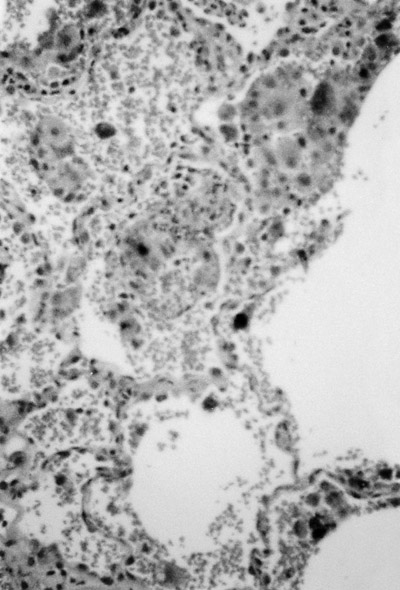

Figure 4. Biopsy of the lung showing capillaritis and arteriolitis.